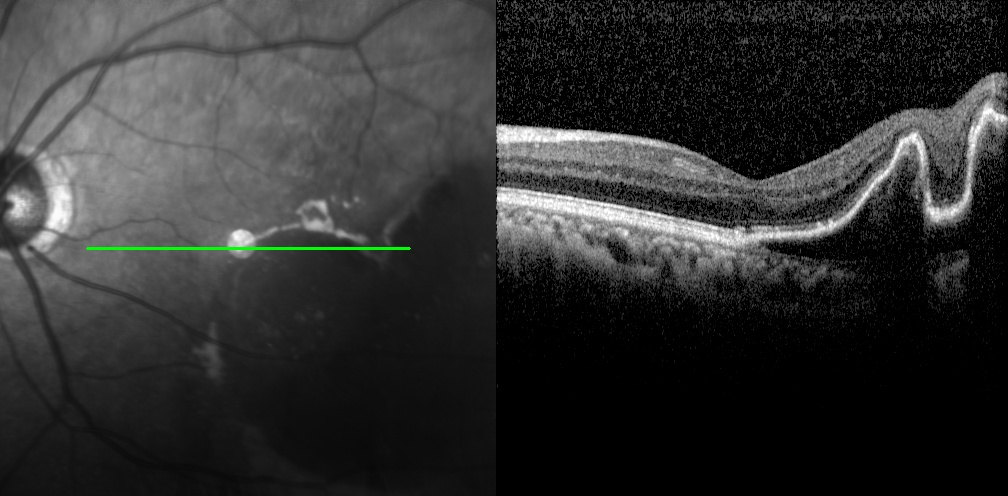

調(diào)整方案后僅半個(gè)月,老李復(fù)查時(shí)左眼終于對藥物產(chǎn)生良好應(yīng)答,眼底狀況明顯好轉(zhuǎn);后續(xù)完成1個(gè)月鞏固性治療,病情得到有效穩(wěn)定控制,視力也穩(wěn)步提升至0.8。

左眼調(diào)整用藥半個(gè)月后檢查圖片